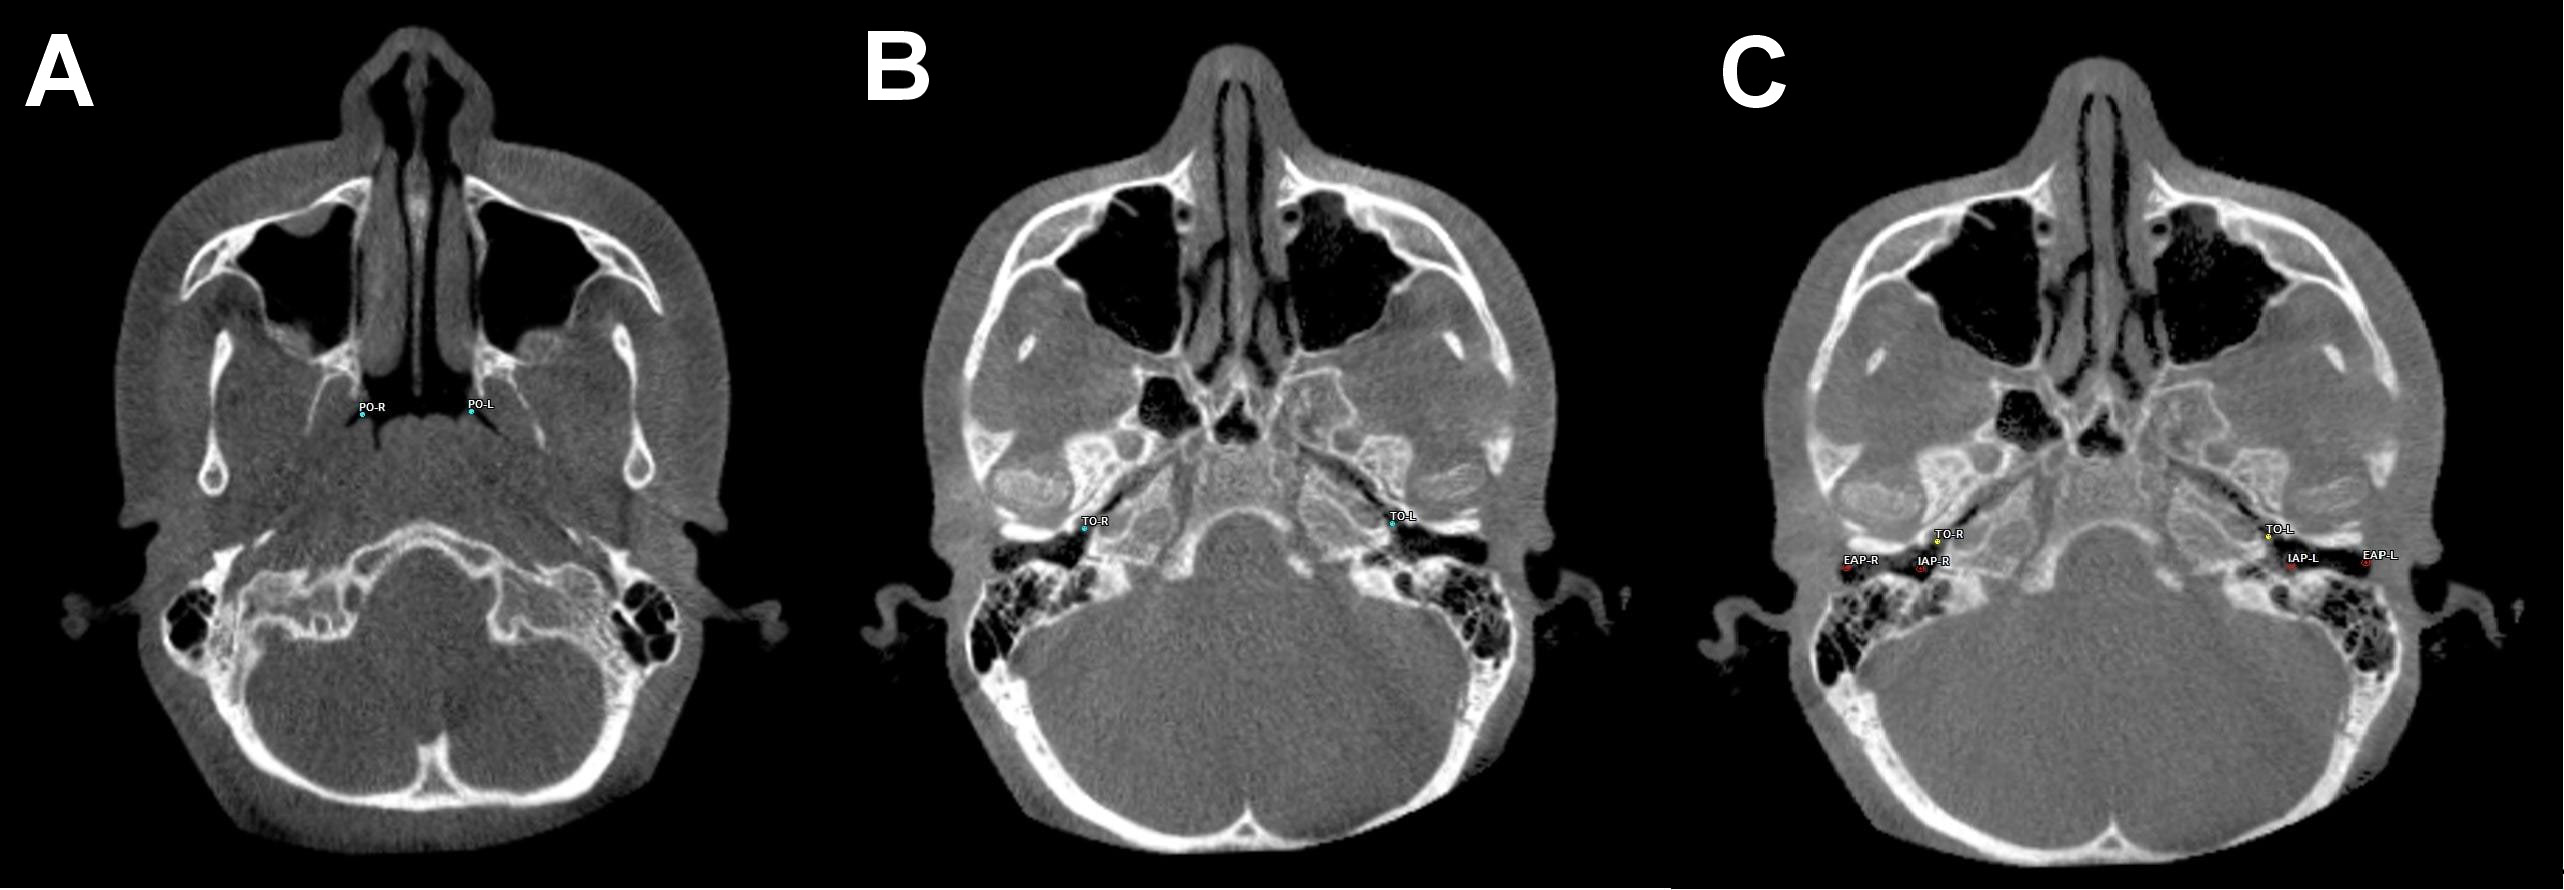

All 3D CBCT images were obtained with patients in a standing position using a CBCT device (ProMax® 3D Mid; Planmeca, Helsinki, Finland). The settings were as follows: 94 kVp; 14 mA; and 27 s. The images were consistent with the field of view (FOV) (20.0 cm × 20.0 cm × 10.2 cm) and voxel size (0.600 mm). The assessment of all CBCT images was conducted in 3D by a single clinician. The SimPlant® O&O image software (Materialise Dental N.V., Leuven, Belgium) was used for 3D image evaluation. The 3D morphological linear and angular parameters are listed in Table 1. The 3D morphological ET traces are displayed in Figure 1, Figure 2, Figure 3.

The comparison of the 3D linear and angular data is presented in Table 3. The mean right ET lengths were 36.26 ±3.10 mm at T0 and 36.13 ±3.08 mm at T1. Before and after RME, the mean left ET lengths were 36.82 ±2.98 mm and 36.82 ±3.12 mm, respectively. The right and left ET lengths did not differ significantly between T0 and T1 (p = 0.513 and p = 0.978, respectively). The mean right ET angle was 22.23 ±3.72° before RME and 22.82 ±4.06° after RME. At T0, the mean left ET angle was 22.33 ±4.22°. At T1, the mean left ET angle was 22.74 ±3.84°, indicating a non-significant difference (p = 0.077 and p = 0.184, respectively). The right auditory tube angle at T0 exhibited a significant increase compared to that at T1 (p = 0.000). The mean left auditory tube angles were 127.87 ±3.28° at T0 and 127.53 ±3.45° at T1 (p = 0.197).

Dinç et al. compared the ET angle and length in healthy subjects and those with otitis media. The ET angles in healthy individuals were 23.0° in females and 24.3° in males.25 The Frankfort horizontal plane was used when measuring ET angles. The angles in our study were slightly lower. In other studies, the mean ET angles with the horizontal palatal plane averaged 34–36° in adults.26, 27, 28 In adolescents, the ET angle with the Frankfort horizontal plane was approx. 22°. The difference may reflect age-related changes and the use of reference planes. The ET angle remained constant after RME on both sides. No prior study has measured the effect of RME on 3D ET angles. Therefore, there was no basis for comparison. We expected that any changes would be similar; symmetrical RME was applied to the mid-palatal suture. No differences in right and left ET length were observed between T0 and T1 (right: 36.26 ±3.10 mm at T0 and 36.13 ±3.08 mm at T1, left: 36.82 ±2.98 mm at T0 and 36.82 ±3.12 mm at T1; p = 0.513 and p = 0.978, respectively). Using two-dimensional images, Bluestone et al. found that the ET length increased as children grew, attaining a final size of 31–38 mm at approx. 7 years of age.12 Takasaki et al. used conventional CT to compare the ET length between children and adults; the ET length in children was 38 mm and 43 mm in adults.28 The CBCT data obtained in the current study was slightly different, presumably due to the imaging modalities. Ha et al. noted that the ET lengths revealed by conventional CT and CBCT differed due to subjects’ positioning, whether in a supine or seated posture.29 Ultra-low-dose CBCT has been demonstrated to optimally detect morphological structures and is associated with reduced radiation, sharper imaging and briefer viewing than CT. Many studies have shown that RME consistently reduces conductive hearing loss and improves ET function in adolescents with maxillary transversal constriction.30 However, the present study found no significant effect of maxillary expansion on the ET length. There are 2 possible explanations for this state of affairs. Other studies have collected audiometric or tympanometric data; however, these studies did not include 3D CBCT linear and angular measurements. Secondly, RME inhibits the infection of the nasal and pharyngeal airways, which may contribute to a reduction in the incidence of otitis. Maxillary expansion improves conductive hearing loss and reduces the incidence of otitis media.